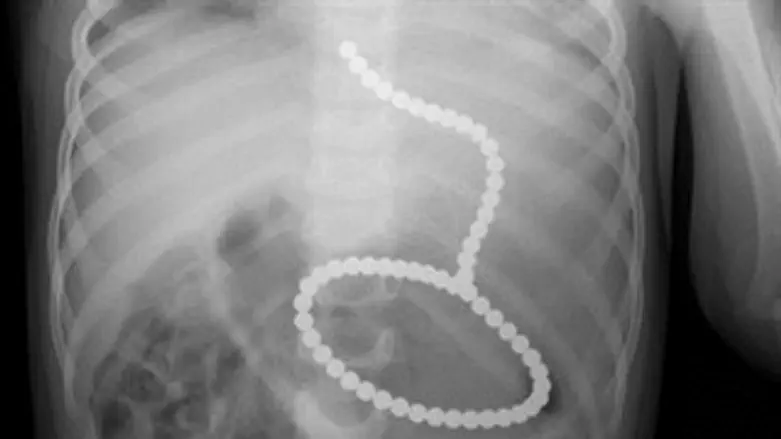

האם סיפרה לרופאים כי מצאה בפיו של הפעוט 2 כדורי מגנט קטנים והיא חוששת שהפעוט הספיק לבלוע כמה כדורים. בתצלום שנערך לתינוק נראו 60 כדורי מגנט, הצמודים האחד לשני בצורה של מחרוזת, בתוך מערכת העיכול.

רופאי גסטרו המתמחים בטיפול במערכת העיכול הובהלו לבית החולים ובתום התייעצות, הוחלט לנתח את הילד ולהוציא את כדורי המגנט באמצעות אנדוסקופ - מכשיר מיוחד המוחדר למערכת העיכול דרך הפה.

לאחר מספר נסיונות הצליחו הרופאים לתפוס את הכדורים והוציאו אותם בהצלחה מבטנו של הילד.